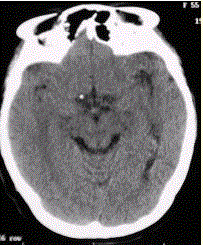

问题 患者男,20岁,癫痫病史。头部CT显示如下图。 动静脉畸形的典型MRI表现是

选项 A.MRT2WI上显示无占位效应的“黑蠕虫”征(血管流空) B.可发生脑、脊髓的任何部位 C.85%发生于幕上,15%后颅窝 D.病变大小不一,由增粗粗大的血管团组成 E.畸形血管团内可见正常脑组织 F.病变可自行消退

答案 ABCDF